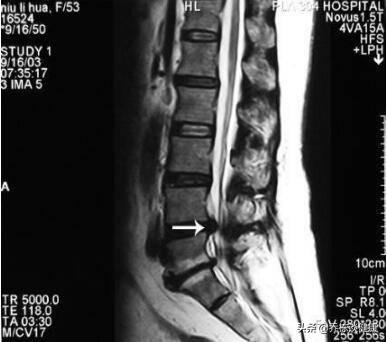

La soi-disant hernie discale lombaire est en fait une rupture de l'anneau fibreux du disque, le tissu interne du nucléus pulposus provenant du lieu de la rupture déborde, la pression stimule la racine nerveuse spinale correspondante, ce qui produit de graves douleurs dans le dos et les jambes. D'après les données cliniques, le groupe de patients souffrant de protrusion lombaire, les lésions de protrusion L3-4, L5-S1 ont le plus de chances d'être atteintes.

hernie discale lombaire

La hernie discale lombaire fait référence à la composition du disque intervertébral lombaire qui se modifie avec l'âge. Sous l'effet des contraintes cumulées, les propriétés physiques et chimiques du disque intervertébral se modifient et, sous l'effet d'une force extérieure, la fibrose se rompt, le nucleus pulposus fait saillie, ce qui entraîne une compression et une irritation des nerfs à l'origine des douleurs lombaires et des douleurs dans les jambes.

Hernie discale lombaire d'avant en arrière